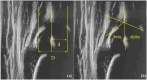

Hip morphometry of the same hip of Figure 1. (a) Femoral head coverage according to Morin et al. (d/D ×100). (b) Alpha angle between base line and bony roof line, beta angle between base line and cartilaginous roof line according to Graf.